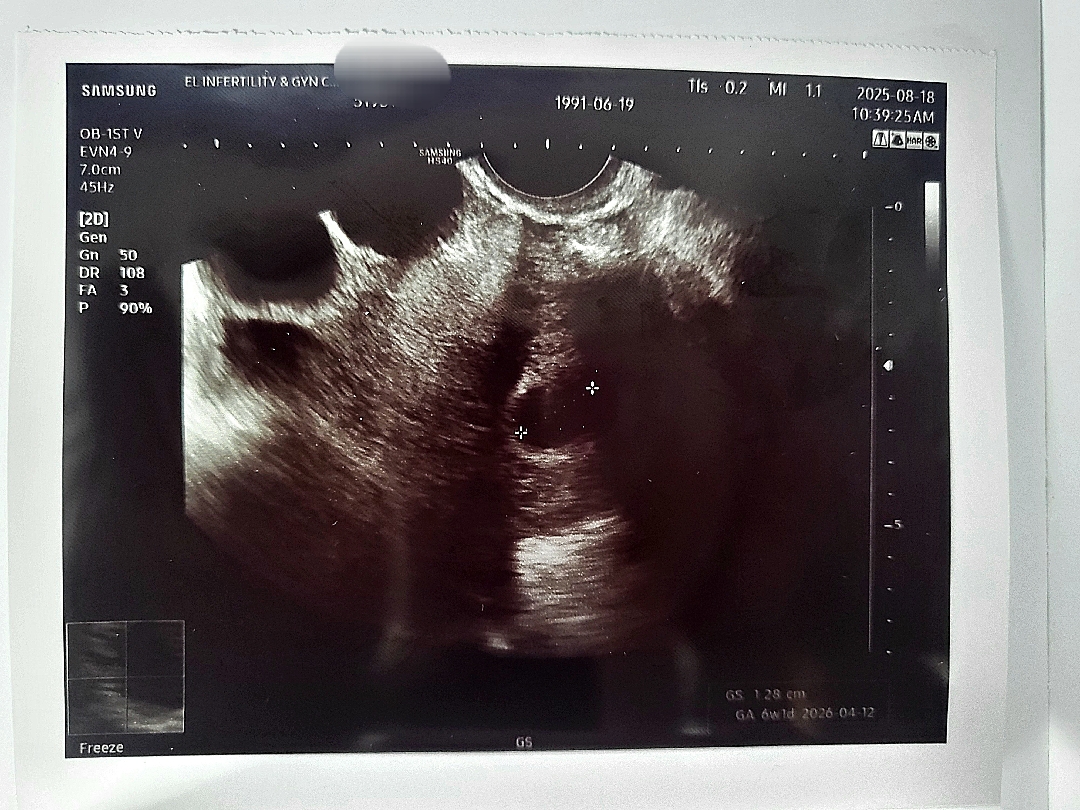

6주래요 그런데 난황이..

아기집 1.28cm 인데요 초음파 볼 때 의사선생님이 아주 작은 흰점을 보여주시면서 달걀에 있는 끈끈이처럼 보이는 거라고 알려주셨거든요 난황이 보였다는 뜻이겠죠?ㅠㅠ

네 정확히 그렇게 했어요! 사진엔 안모이는데 초음파에서 아주작은 흰점같은거... 난황이라곤 안 하셨고 "보이죠?" 이렇게하셨어요ㅜㅜ감사해요